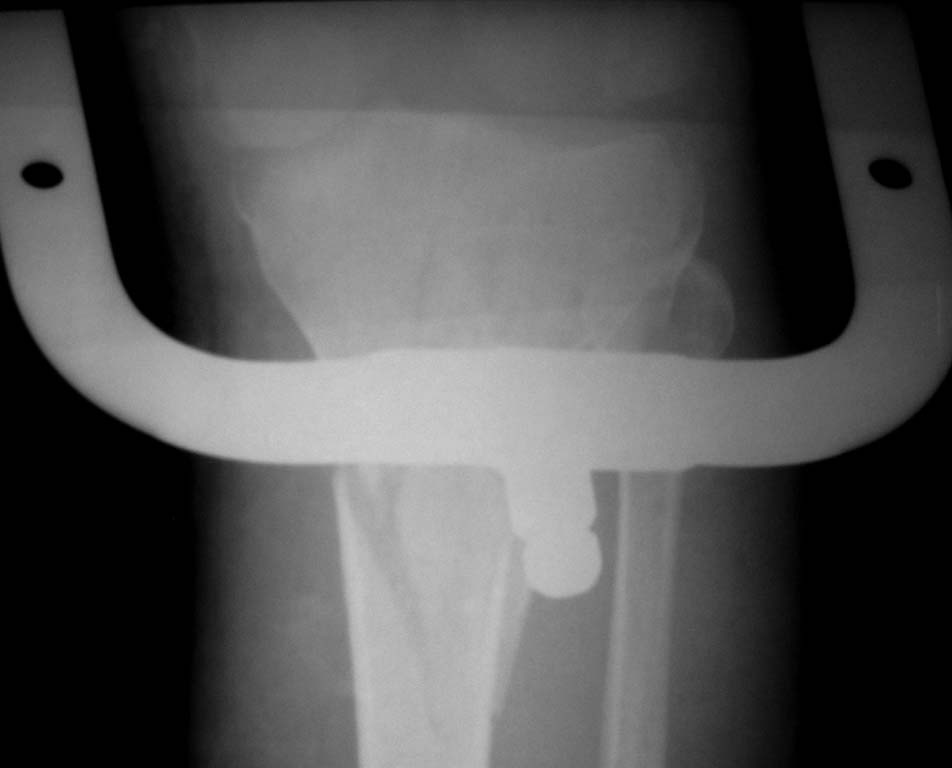

Нужен совет. Открытый перелом в\3 диафиза с оскольчатым переломом дистального метаэпифиза бедра.

Закрытый оскольчатый внутрисуставной перелом проксимального отдела большеберцовой кости той же конечности.

При поступлении ПХО ран, скелетное вытяжение. Рана зажила первичным натяжением. Осложнилось правосторонней пневмонией. Предстоит выбрать тактику оперативного лечения и камими имплатнатами.